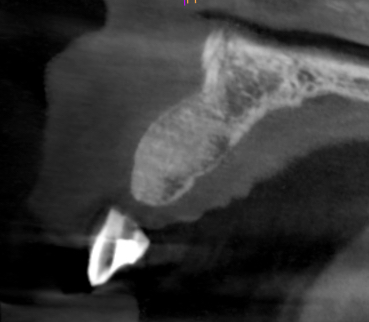

Clinical and CT scan assessment confirmed that the UR2 suffered from extensive bone loss with complete loss of the labial plate and was associated with a large periapical lesion which extended palatally and laterally towards the UR3. The UR3 tested positive to vitality testing.

Healing was uneventful and following a seven-month maturation period, a CBCT scan confirmed the presence of the MinerOss®/autogenous bone graft and a favourable volume of bone. However, it was noted that the soft tissues covering the bone graft were thin with an absence of interdental papillae. It was determined that a connective tissue graft would be required as part of the next surgical procedure to improve the soft tissue volume and lead to the creation of papillae during the prosthetic stages.

Healing was uneventful and following a seven-month maturation period, a CBCT scan confirmed the presence of the MinerOss/autogenous bone graft and a favourable volume of bone.